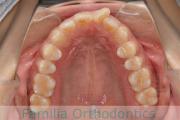

上の前歯の並びが気になるのできれいにしたい、ということで来院されました。マウスピース型矯正装置のひとつ、インビザライン/InvisalignR(薬機法および医薬品副作用被害救済制度の対象外)を用いて治療しました。

非抜歯で2年弱、20回程度の通院で治療が完了しました。

マウスピース矯正は、患者さんの協力に治療結果が左右されるところはリスクと言えるかもしれません。